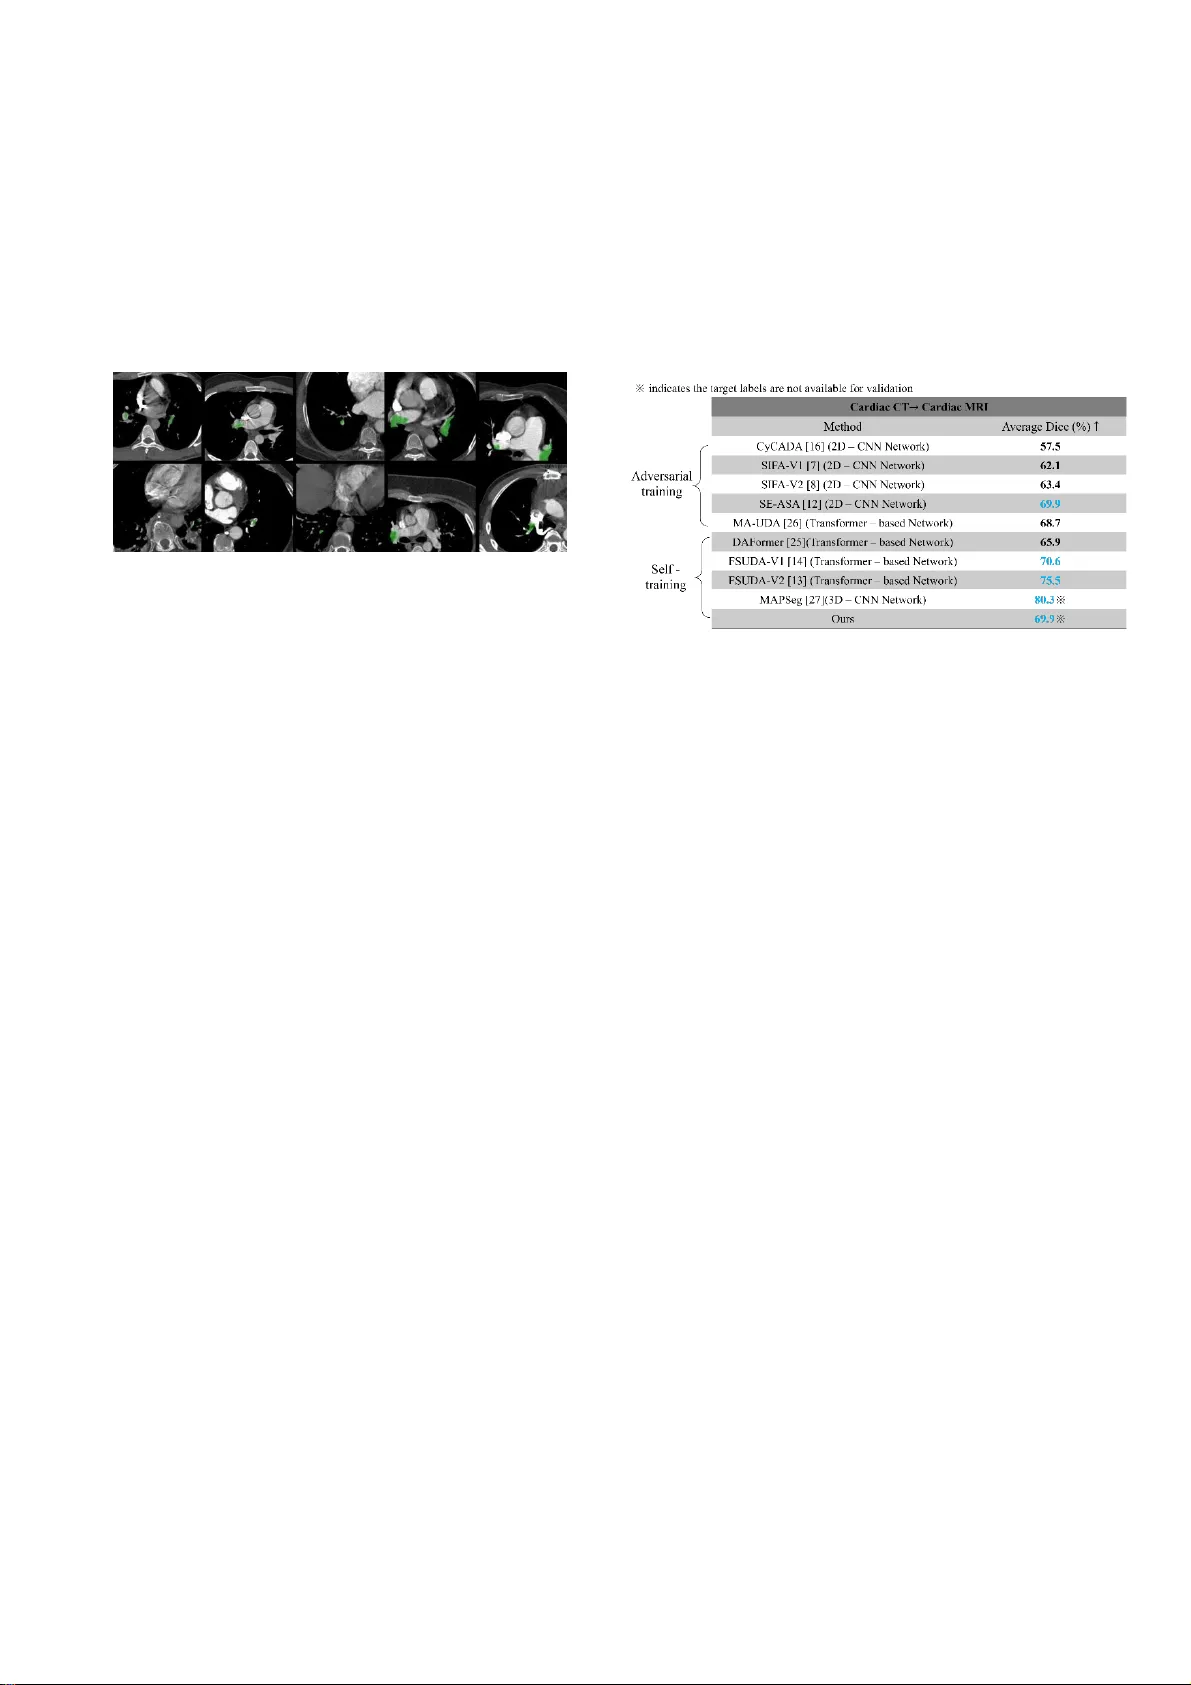

1 Using Uns upervised Do ma i n Adaptati on Semantic Seg menta t ion f o r Pulmonary Em bo l ism Dete ction in Computed T omog r aphy Pulmonary Ang iogram (CTPA) I mages W en -Liang Lin 1 * , Y un -Chien Che ng 1 *, 1 Depa rtmen t of Mecha nica l Engine ering , College of Engin eering, Nation al Y an g Ming Chia o T un g Univ ersity , Hsin -Ch u, T a iwan *Co rresp onding autho r: lightne il9.en10@ny cu .edu.tw , yc ch eng @nycu.edu.tw 2 Abst ra ct While dee p l ea rning has d emonstrated consider able promise in c omputer-aide d diagnosis for pulmonary embo lism (PE), pra ctica l deploy ment in Comput ed Tomo graphy Pulmonar y Angiography ( CTP A) is often hin dere d by " do main shift" and the prohibiti ve cost of e xpert a nnotations. To a ddress t hese c hallenges, an unsupe rvised do main ada ptat ion (UDA ) fra mewor k is proposed, uti lizing a Tr ansfor mer ba ckbone a nd a Mea n- Tea che r ar chitectur e for c ross- ce nter semantic segmenta tion. The primary f ocus is place d on enha ncing pseudo-la bel re liabili ty by lear ning deep s truc tural informa ti on w ithin the featur e spa ce. S pec ifica lly, three modules a re int egr ated and de signed for this task: ( 1) a Prototype Align ment (PA) mec hanism to reduc e ca tegory-le vel distributi o n d iscre panc ies; (2) Global and Loca l Contrastive Le ar ning (GLCL) to capture both pixel-leve l topol ogica l relationsh ips and global sema ntic re prese ntations; a nd (3) a n Attention -ba sed Auxiliary Loca l Prediction (AAL P ) module designed to reinfor ce sensitivity to sm al l PE l esions by automatica lly extra cting high -infor matio n s l ices fr om Tra nsforme r attention maps. Expe rimental validat ion c onducted on cr oss-cente r datasets (FUMP E and CAD-PE) demonstra tes signific ant per forma nce ga ins. In t he      task, the I oU incre ased from 0.1152 to 0.4153, while t he      task saw an improve ment fr om 0.1705 to 0.4302 . Furthermore , the propose d method ac hieved a 69.9% Dice score in the     cr oss-modality task on the MMWH S datase t without uti lizing any tar get-domain labels for model selec tion, c onfirming its r obustne ss and gene raliza bilit y for diverse c linical environme nts. Keyw ords: Dee p learning, Pulmonary e mbolism, V ision Tra nsformer , Comput ed T omography Pulmona ry Angiogra phy, Unsupervise d do main adapta tion, Seman tic segmentati on 1. Introdu cti on Pulm o nar y e mboli s m ( PE) is a l ife-thre atening ca rdiovascula r condition re quiring prompt diagnosis a nd immediate cli nica l int er ventio n. Computed Tomography Pulm o nar y Angiography ( CTP A) is cur rently regar ded a s the clinica l gold s tanda rd for PE di agnos i s [1] due t o its superior spatial re soluti on and diagno stic acc urac y. Howe ver, manual interpr etation of CTPA scans remains a formidable cha llenge for radiologist s; PE lesions, par ticularly t hose at the sub -segme ntal level, are often re markably sm all and ca n be easily miside nti fie d or over looked amidst complex pul monary vascular structure s. To mitigate the risks of misd iagnosis and re duce the workload of clinicians, deep l ea rning-based Comput er -Aided Diagnosi s (CAD) sys tems have shown significant progre ss in auto mat ing PE detection. Early studies employing Convo lut io nal Neur al Networks (CNNs) , such as those by Cano-Espinosa et al. [2] and Long et al. [3], demon strate d t hat dire ct segmentation strate gies and probabi lity-driven anc hor mecha nisms could effe ctively detect sub -segme ntal emboli wi thi n single-ce nter datasets. Similarly, Tr ongmetheer at et al. [ 4 ] integra ted attention mecha nisms into U-Net a rchitec tures to enhanc e the sensi tivity of detec ti ng minute lesions in small vessels. Howe ver, these supervise d appr oaches rely on the Inde pendent and I dentica lly Distributed (IID) assumption. In clini ca l reality, medica l images ar e subject to significant "d omain shift" ca used by var iations in scanne r protocols, contra st timing, and patient demogra phics [5]. C onseque ntly, m odels t ra ined on source domains often fail to gene ralize to unseen target domains (out-of- distributi on data) . While r etra ini ng models on targe t data is a theor etical solution, t he prohibitive cos t of pi xel-leve l anno tation by radiolog ists re nders fully super vised transfer l earning imprac tical. To addr ess this, Unsupervised Domain Adaptat ion (UDA ) has be come a key r ese arch direc tion tha t se eks to transf er knowledge lea rned from a labeled source dom ain to an unlabele d targe t domain w ithout re quirin g targe t -domain annotations [6]. Extensive resea rch ha s explore d va rious appr oache s for UDA. Th ese methods ca n gene r ally be grouped into three ca tegories: image- level alignment, adve rsa rial lear ning, and self- training. Ima ge-leve l approa ch es span from Cycle GAN-ba sed tra nslation methods [7-9], which ca n be computational ly proh ibitive, to l ig htweight alter natives such a s Fast F ourier Tra nsform (FFT)-based style transf er [10- 14]. In parallel, fe ature - or output-leve l adve rsar ial alignment [15-17] ha s been widely explore d, yet it is of ten diff icult to train r eliably due to the sensitivity of min – max optimization. The se li mi tations have moti vate d increa sing int er est in self-tr aining, whe re Mea n-Tea cher [18-19] f ra meworks are fre qu ently adopted for their relative stabili ty. N ever theless, a centra l bottleneck remains: pseudo-labe ls on t he target domain ar e inevitably noisy, l ea ding t o err or acc umulation in highly class-i mbalanc ed sce narios like PE segmentatio n. Beyond the choice of adaptation strategy, the bac kbone arc hitecture also plays a critical role. Many UDA pipelines were originally deve loped on standar dized CNN bac kbones. Howeve r, C NN- based models have increa singly be en o utperf ormed by St ate- of- the-A rt (SOTA) Transf ormer architectur es [ 20-22 ]. B y lever aging self-attention t o m odel long -r ange semantic depe ndencie s, Transf ormers c an over come t he l oca lity of CNN rec eptive fie lds a nd often exhib it stronge r gene raliza tion [23-24]. B uilding on th is trend, DAFormer [25] was among the first t o integr ate a Tra nsformer backbone into a Mean-Teache r UDA fra mewor k, achieving SOTA perf ormance on the       benc hmark. I n medical imaging , 3 MA - UDA [26] fu rther advance d this direc tion by explicitly alignin g repre sentations at both the pixel and attention levels t o mitiga te cross-modality domain shift. Its key i nnovati on, the M eta Attention mechanism, establishes hier ar chica l co rre lations across mult i -he ad attention maps, enabling eff icient multi-leve l alignment without i ntroducing multiple dis cr imina tors as requir ed in adver saria l approa ches. In the c urre nt landsca pe of medical UDA , MAPS eg [27] represents the pea k of non- adver sarial S OTA, ac hieving an im pre ssive 81.32% Dic e score on     tasks. By a bandoning unstable a dversa rial lea rning for a robust Mean-T eac her m ec hanism, it succe ssfully integra tes ana tomi ca l priors via a Global-Local Coll abor ation (GLC) module . Notab ly, MA PS eg established a new benchmar k by proposing a fair model selec tion mec hanism, a ddressing the co mmon but clinically i mpractica l practice of relying on t ar get- domain labe ls for vali dation. Howe ver, despite these bre akthroughs, significant barrie rs re main. Fi rst, MAPSeg’s re liance on 3D CNNs and 3D VA Es imposes ex cessive c omputational ove rhe ad and m emory demands, ra isi ng the threshold for hardware -c onstrained clini ca l environme nts. Second, and most critically for P E detec tion, t he GLC m odu le employs random cropping strate gies. Given that PE l esions occ upy a minute fr a ction of the volume, random sampling fre quently yields bac kground-only pa tches, l ea ding to inef fec tive ana tomi ca l alignment and t he loss of critica l lesion - re lated conte xt. To bridge these gaps, t hi s study proposes a Tra nsformer -base d Mean-Teacher UDA f r ame work tailored for cr oss-cente r PE detec tion. Unli ke traditional CNNs, a Mix Vision Transfor mer (MiT) backbone [ 22 ] is employed to ca pture long -r ange sema ntic depe ndencie s while preserving high -r esolution details for small lesions. The pri mary contribution l ies in the integra tion and design of three feature- spa ce alignm ent modules to enha nce pseudo-labe l re liability: (1) Prototype Alignment (PA) to m in imi ze categor y -leve l distribution sh ifts; (2) Global and Loca l Cont ra stive Lea rning (GLCL) , augmented with a momentum queue, to captur e topolog ical re lationships a nd globa l semantics without l ar ge-ba tch require ments; and (3) an Attention - base d Auxiliary Loca l Prediction (AALP) mo dule. Unlike ra ndom cropping, AA LP uti lizes Tr ansfor mer attention m aps to exp licitl y extrac t lesion -rich re gions, enf orcing anatomical consistency betwee n local and global views. The main contrib utions of t his study are summarize d as follows: (1) A computational ly eff icient Tra nsforme r-base d Mea n-Tea ch er UDA fr amew ork is deve loped for CTP A PE segmenta tion, balancing per formanc e and resour ce constraints. (2) Three feature space alignm ent modules (PA, GLCL, AALP) are i ntegra ted and designed to ac tively im prove pseudo-labe l quality and addr ess the cha llenge of detec ting sm all P E lesions. (3) An Attention-based A uxili ar y Loca l P re diction (AA LP) module is proposed to re place random cr opping, si g nifica ntly enhanc ing sensitivi ty to tiny objects. (4) Experiments on cross-ce nter (FUMPE, CAD- PE) and cross-modality (M MWHS) datasets demonstra te that the propose d met hod ef fec tively mi tigates domain sh ift and a chieve s robust pe rfor mance unde r a strictly unsupervise d model selec tion setting. 2. Related Wo rk 2.1. Uns u pervise d Doma in Ada ptation UDA aims to minim ize the expe cted risk on the targe t domain by aligning the source and targe t distributions, as theor etically bounded by Ben-David et al. [28] . Current stra tegies fa ll int o t hree ca tegories: (1) Image- Level Alignm ent: These m ethods reduce visual discr epanc ies in the input spa ce. While CycleGA N-base d approa che s [7-9] succe ssfully align texture s, they entail high memory usage and training insta bil i ty due t o the require ment of multi p le gene rators and discr iminators. Alterna tively, F ourier Tra nsform (FF T) based methods [10-14] decompose image s into amplitude (style) and phase (structure ). By swapping the low- fre quenc y ampli tude spectr um of s ourc e images with that of t ar get images, style t ra nsfer c an be ac hieved effic iently without l ea rnable parame ters. Similarly, histogr am matching aligns intensi ty distributions. Given the computational cons traints in clinical sett ings, this s tudy adop ts ef ficient FFT and histogram matc hing t ec hniques for preliminary in put-leve l alignme nt. (2) F ea ture-L evel Adversarial Alignment: Inspired by GANs, m ethods like Adapt SegNet [15] and CyCADA [16] employ domain discr iminators to enf orce f ea ture i nvar iance. Although effe ctive, adve rsar ial tr aining is notoriousl y unstable and sensitive to hype rpar ameters. Consequently, this study opts f or a more stable self-tra ining pa ra digm . (3) S elf- Training and Mea n-Tea ch er : S elf- training gene rate s pseudo-labe ls for the unlabe led tar get domain to guide l ea rning [10, 25, 27, 29 -37]. The Mea n-Tea ch er framew ork [18- 19], utilizing Tempora l Ensembling, has become a standard for stabilizing these ps eudo-la bels. Howeve r, the quality of pseudo-labe ls remains a bot t lenec k. While t hre shold-based filt er ing and uncerta inty estimation [38] are common, they are passive strate gies. R ec ent works have explored m eta- 4 lear ning [39] for noise corr e ction, but computational costs remain high. This study foc uses on improving pse udo-labels through a ctive structura l lear ning in t he f eatur e spac e. 2.2. Structural L ear ni ng in Feat ure Space To enha nce feature discriminability, Pro totype Alignment ( PA) a nd Cont ra stive Lea rning have been introduce d t o UDA. PA align s class-specif ic centroids betwe en domains [12], r educ ing ca tegory-level s hifts. Howe ver, PA alone may fail for cl ass-imbalance d data like PE, where ce ntroids a re biased by bac kground noise. Contrastive lea rning pulls posi ti ve pairs closer while pushing negatives apart. Liu et al. [13] proposed a Dual Contrastive fra mework comb ining gl obal and loc al contra stive los ses to capture both s emantic layout and pixel-leve l t opo logy. A l i mitation of such approa ches is the depe ndency on l arge bat ch sizes fo r suffic ient nega tive samples. To mit igate this, this study incorpor ates a m omentu m queue (Mo Co) [40] in to the GLCL module, enabling eff ective contrastive learning under lim ited har dwar e re source s. 2.3. Context -Awar e Modeling a nd Limitatio ns of Random Crop Integr ating global a nd loca l context i s vi tal for ensuring ana tomi ca l pl ausib ility. MA PSeg introd uce d a Global-Loc al Collaboration (G LC) modu le that enfor ce s consistenc y betwee n global fea tures and l oca l patche s. While ac hieving S OTA results, MAPSeg relies on ra ndom cropping t o selec t loc al patche s. In PE detec tion, wher e lesions ar e sparse and small, ra ndom c ropping pre dominantly s ele cts bac kground re gions, render ing the local-globa l alignment ineffe ctive. To addre ss this cr iti ca l flaw, this study proposes the Attention-base d Auxiliary Loca l P redic tion (AA LP) m odule, which lever age s the T ra nsformer 's inher ent attention maps to intelligently l oca te and crop lesion -infor mative regions, ensuring me aningful context a lignment. 3. Mate rial and Meth ods 3.1. Datase ts for UDA Trai ni n g To evalua te the g ener alizability of the proposed UDA fra mework in clinical sc enar ios, two types of ada ptation tasks were conduc ted: bidirectional cross- ce nter adaptation using C TPA images and cross- modality adapta tion usin g ca rdiac sc ans. 3.1.1. CTPA Datase ts For the cross-ce nter adaptation experiments, two publicly ava ilable C TPA datasets with expe rt semantic annotations for PE wer e ut ilized: t he F er dowsi University of M ashha d’s Pul monar y Embolis m (FUM PE) datase t [4 1] and t he Computer Aided De tection for Pul m onary Embolism Challenge (CAD- P E) dataset [42]. Specific ally, t he experiments in t his resea rc h were conduc ted using image sequenc es from 33 sel ec ted patients from the F UM PE data set and 91 patie nts from the C AD-PE dataset. A critical aspe ct of the experimenta l design is the patient-wise partitioni ng of data, ra ther than slice-w ise par ti tioning, to be tter re flec t authentic clinica l conditions and preve nt data leakage . S pec ifically, the training and validation sets for FUMPE and C AD- PE wer e partitioned i nto 29/4 and 80/ 11 patients, re spectively. In t he UDA training phase, t he model has ac cess t o annotations only from t he source dom ain, while the t ar get dom ai n remains entirely un labele d. For instance , in t he      task, the fra mewor k l earns from the l abe led FUMPE training set and perfor ms domain align ment u sing the unla beled CAD-PE training set, wi th per formanc e f inally e valuate d on the CAD-PE va lidation set. 3.1.2. Cardiac CT-MRI Dataset To ensur e a fair comparison with ex isting medical UDA li ter ature , we conduct cross-modality adapta ti on expe riments on the Multi-Modality Whole H ear t Segmentation ( MMWHS) da taset [ 43]. MMWHS comprise s 20 MRI scans and 20 CT scans with annotations for seven cardia c anatomica l s truc tures. Foll ow ing the pre vale nt st anda rds in UDA researc h, this study focuse s on four ke y structure s: Myocardium of t he Lef t V entricle (MYO) , Left Atrium B lood C avity (LA C), Lef t Ventr icle Blood Cavity (LV C), and Ascending Aorta (AA). To ensure dir ect comparabilit y with S OTA methods, we adopt the same training/val idation split protocol a s specifie d in [8]. 3.2. Ex p er im ental Pr oced ure The overa ll expe rimental proc edure of this st udy is illust ra ted in Fig. 1. Fol l owing the dataset partitioning strate gies detailed in S ec ti on 3. 1, t he pr oposed UDA training fra mework i s impl eme nted to deve lop t he Figure 1. Exper iment proce ss 5 semantic segmentati on model. To comprehe nsively eva luate the perf ormanc e and clinical ut il ity of the system, the fol lowing tes ts wer e conduc ted: (1) Validation of the UDA frame work’s effe ctivene ss on the MMWHS dataset for c ross-moda lity ada ptation. (2) Assessment of the perf ormance and ada ptability of the Tra nsforme r-base d architectur e in UDA ta sks. (3) Validation of the UDA fra mework on CTPA datase ts, spec ifically evalua ting the perf ormanc e gain in detec ting m i nute pu lmonary em bolism lesions through fe ature space structura l learning. (4) Ablation studies on e ach critical UD A component to ver ify their individual con tributio ns. (5) A fair compar ison betwee n the propose d UDA training fr amewor k and e xist ing SOTA methods. 3.3. Data Pr eproc essing The ra w C TPA data is pr ovided in DI COM or Nea rly Raw R aste r Data (NR RD) forma t, whe re intensitie s a re expr essed in H ounsfield Units (HU) t o re flect t issue ra diation a bsorption. The orig i nal HU r ange , typically spann ing from -1000 t o 3000, often re sults in poor contra st betwe en PE l esions and surrounding pulmonary s truc tures. To addre ss this, an emp irica l HU window is app lied to clip t he intensity range to [ -200, 500], foll owe d by normaliza tion to [0, 1]. Furthermore , as the pulmonar y arte ry is typically situated a t the image ce nter, the images are croppe d t o a resolution of     to reduc e computational redunda ncy a nd over head. The visual enha nceme nt achieve d through this HU window ing i s il lust ra ted in Fig. 2. For the MMWH S datase t, the pre proce ssing protocols str ictly adhere to the standar ds established in [8], i ncl uding rando m cropping to a size of     to ensure t he di re ct compar ability of expe rimental results. Figure 2. (a ) Befor e applying a H U window (b) Afte r applying a H U window 3.4. UDA Tr aining Metho ds 3.4.1. Problem De finition Given a source domain image set    󰇝   󰇞    with i ts corre sponding pixe l -leve l ground truth labels    󰇝   󰇞    , and a rela ted targe t domain image set    󰇝   󰇞    , wher e   and   re prese nt the total sample c ounts for ea ch re spec tive domain. Our ob jective is to construct a r obust sema ntic segmentation model   . Conventional models optim ized sol ely on s ourc e-domain data f reque ntly e xpe rie nce a subst antial drop in pre dictive a ccur acy when a pplied to the targe t environme nt, a conseque nce of the domain s hift eff ect. UDA aims to mitigate this discre pancy withou t relying on targe t-domain annota ti ons. By im p lementing mecha nisms such as image-le vel t ra nslation or fea ture- spac e alignment to minimize distributional va rianc es, UDA fac ili tates t he migra tion of sourc e-lear ned knowledge to the targe t domain. This process e ventually enha nces the m odel’ s di agnostic ef fic acy in spe cia lized clinical ta rget-domain a pplications. 3.4.2. Ove rall UDA Trainin g Frame work The conce ptual conf iguration of the deve loped UDA training fra mework is presented i n Fig. 3, where the gre en and red l ines identify the i nfor mation flow for t he source and t ar g et dom ains, respec tively. The overall fra mewor k i s structure d i n to thr ee essential phases. The proc ess st ar ts with style-tra nsfe r data augmenta tion during the in iti al processin g to m it igate visual discre pancie s acr oss the domains. Subseque ntl y , a Mea n- Tea che r self-training sc heme with consiste ncy re gulariza tion is employed ; the tea che r networ k produce s pseudo-la bels for unlabe led tar get image s, providing supervisor y signals to t he st udent model despite the abse nce of targe t-domain annotation s. F inally, to further optimi ze feature repre s entation, t hre e specialize d modules for fea ture space st ruc tural lear ning ar e integra ted i nto t he training proce ss. These modules are designed to m ine semantic structure s wit h in the latent spac e, which im prove s pseudo-labe l reliability and enha nce sensiti vity to the f ine boundarie s of s mall l esions. Deta iled formulations and implementat i on detai ls are provided in the f ollowing sub sec tions. Figure 3. Over all UDA t ra ining fr amew ork 6 3.4.3. Segme ntation Netwo rk Arc hit ec ture As established in [25], Transfor mer-ba sed models exhibit superior pe rfor mance and fle xibility over classic al CNNs when applied to UDA semant ic segmenta tion. Conse quently, the Mix V ision Tra nsformer (MiT-B5), pre tr ained on Image N et [44], serve s as the encode r in our architecture . The decoder utili ze s a Featur e Pyramid Ne twork (FPN) following the fra mewor k outli ned in [45] . The FPN arc hitecture is par ticularly critica l for enhanc ing t he detection of small lesions, as it eff ectively integr ates high-resolution details and rich semantic information from shal low and deep layer s, respe ctively. F inally, these combined fea ture maps are proce ssed by a s egme ntation head to produce pixel-leve l class pre dictions. 3.4.4. Style Tr ansfer and Da ta Augmenta tion In this study , the i mage sets gener ated t hrough data augmenta tion are denoted by 󰇝             󰇞 ,. The sets 󰇝      󰇞 consist of sour ce and t ar get i mage s proc essed via conventional augmenta tion s tra tegies, such as Gaussian blurring, rotations, a nd random pixel dropout. Converse ly , 󰇝      󰇞 denote im age s proc essed via t he style transfe r modules (Four ier-base d augmenta tion or Histogr am Matching) direc tly mini mize input-space domain disparit ies. For Fast Fourier T ransfor m (FFT) Data Augmentat ion : A s establi shed in prior UDA re sear ch [10- 11 ], F ourier -base d style transf er has demons trate d significant effe ctiveness in enha ncing data diversity and improving perfor mance across var ious UDA t asks. This technique re lies on the decompo sition of fr equenc y - domain i mages into their re spec ti ve pha se a nd amp lit u de constituents. Ge nera lly , the a mplitude component ca ptures st ylistic attribu tes like texture and i n tensity , wher ea s the phase compone nt ma intains t he esse nti al semantic a nd structura l layout of the i mage. For a sour ce image        (whe re  ,   and   si gnify height, wi dth, and cha nnel i ndices), the F ourier transf orm  i s ut ili ze d to obtain the am plitude spectr um   and the phase spectr um   as follows: 󰇛   󰇜󰇛    󰇜     󰇛    󰇜   󰇡       󰇢   (1) wher e 󰇛   󰇜 ar e coordinates in t he spa tial doma in, 󰇛   󰇜 ar e coor dinates in the fr equenc y domain, and  is the im agina ry unit (      ) . Sim ilarly , the ampli t ude   and phase   of a target image   are obtained. Subsequently , a binary mask   is defined to i solate the centra l low-fre quen cy components (set to 1) whil e setting all rema ining fre quenc ies to 0, the reby en abling the source im age to be rendered i n the targe t style. The ar ea of this region is controlled by the pa rame ter  . The style transf er ope ration is formulate d as:                     (2) Her e, the sym bol  signifie s the Hadama rd (eleme nt - wise) product. This strategy ensure s t he preser vation of high-fr equenc y source s truc ture while in tegrating l ow- fre quenc y target cha rac teristics, there by expanding the diversity of the training data. Finally , the hybr idized amplitude    is combined with t he original pha se   via the inver se Fourier transform   to rec onstruct the stylized image    :       󰇛       󰇜 (3) For Hi stogr am Matc hing: This classical image proc essing technique ma ps the intensity di strib ution of a source i mage to that of a targe t im age to achie ve alignment. For    and   , the pixel in tensities are first normalize d into  discre te bins within t he r ange 󰇟     󰇠 . Letting   be the intens i ty val ue of the  -th bin, t he proba bili ty d istribution   󰇛   󰇜 is define d as:   󰇛   󰇜     (4) wher e   is the number of pixels w ith intensi ty   , and    i s the im age size. A si m ilar distribut ion   󰇛   󰇜 is calcula ted for the targe t do main. By computing the cumulative distrib ution f uncti ons (CDF) for both domains, a m appi ng func tion is esta blished to adjust the intensity distributi on of the source image to match the targe t, resulting in the stylize d outpu t     . 3.4.5. Me an Teacher and Co nsistency Regulari zati o n To mitigate the domain shift betwee n the s ourc e and targe t domains , we a dopt a self- training s trategy based on the Me an-Te ac h er par adigm [ 18]. This iter ative fra mewor k generates online pseudo-labe ls t o supe rvise lear ning on unlabeled target i mage s. The fra mewor k consists of a tea che r model  󰇛     󰇜 and a student model  󰇛     󰇜 , w hich sha re identica l ar chitectur es. Instead of being updated by bac kpropaga tion, the teac her’ s weights are adjusted at eve ry t ra ining st ep  t hrough the Exponentia l Moving Aver age (EMA) of the student’s we ights :           󰇛   󰇜    (5) wher e  is a hyperpa ra meter s et betwee n 0.99 and 0.999, re spectively, ac cording t o d iffer ent training stages. This mecha nism is designed t o stabil ize t he opti mization proc ess, ensuring the ge ner ation of re liable, hi gh-fidelity pseudo-la bels as the mode l converge s. During the pseudo-labe l gene ration phase, the teac her m odel produces a probability m ap   for th e targe t image. While convent ional met hods often employ a fixed threshold  to conver t these m aps into bi nar y 7 pseudo-la bels, the tea cher model is prone to noise in the ea rly stages of train ing. In the c on text of pulm onary embolism de tection, whe re c lass imbalance is se vere and lesions occ upy a minute fra ction of the image, a fixed threshold ca n l ea d to conf irmatio n bias, as the model tends to classify am biguous re gions as background. To miti gate thi s, an e ntropy-based dyna m ic filtering mecha nism is adopted. The entropy for ea ch pixel is ca lculated a s follows:      󰇛     󰇜       󰇛     󰇜 (6) wher e  󰇛    󰇜 re prese nts the predic ted p robability of targe t i mage   belonging to class  . By mi n imizi ng this entropy, the model is dr iven to m ake high -c onfidenc e pre dictions on unlabele d targe t data . In prac tice, pixels ar e ra nked by their e ntropy value s, and only the top 80% with the lowest entropy (highest confidenc e) are reta ined as valid pseudo-labe ls for consistenc y lo ss calcula tion. The remaining 20% are maske d as unre liable, pre v enting lear ning st agna tion ca used by overly rig id t hre sholds i n ea rly itera ti ons. Furthermore , a consistency regular ization st ra tegy utili zing strong and wea k data augme ntations is integra ted to enha nce performanc e. S pec ifically, the student and t ea che r models receive strongly and wea kly augmente d versions of the i nput, respe ctively, an d ar e re quired to produce consistent pre dictions. Bot h t he source domain se gmentation l oss    and t he t ar g et domain cons istency loss   are ca lculated using Dice L oss, defined a s:                                    (7) wher e   is the pre dicted probability from the student model and   re prese nts the t ar get label. F or   ,   is the source -domain ground truth, w here as for   , it denotes the teac her-ge nerated onli ne pseudo-la bel. Dice Loss is partic ularly ef fec tive for medica l image segmenta tion a s it i s less sens itive to class imbalance , stabilizing the training proc ess dominated by bac kground pixels. Finally, whi le filter ing low -c onfidenc e pse udo- labels is essential, i t may not be suffic ient to e liminate all noise. To ena ble the model to ac tively learn t he st ruc tural informa ti on of the feature spac e and mine corr elations betwe en domains, thi s study introduce s three spe cialize d fe ature lear ning modul es: Prototype Align ment (PA), Global a nd Local Contra sti ve L ear ning (GLCL), a nd Attention-base d Auxiliar y Local Prediction (AALP). These modules op timize fea ture represe ntation from diffe rent perspectives, th ere by improving pseudo-labe l quality and over all segmenta tion e ffica cy. 3.4.6. Proto type Alignme nt (PA) The Prototype Align ment (PA) mecha nism implemented in t h is study ai ms t o resolve t he fea ture distribution sh ift common ly encounte red i n unsuper vised domain adapta tion. By perfor ming class-le vel centroid alignment, the fr amew ork promotes the c lustering of fe atures with i dentica l semantic l abe ls — such as pulmonary vascular structure s — within the l ate nt space ac ross both domains. The proc edure s tar ts with the extrac tion of latent re prese ntations  from the p enultimate l aye r of th e enc oder. For the source and target dom ains, the m odel utili ze s the sourc e ground t ruth    and the targe t onli ne pseudo-la bels   to extra ct class-spec ific fea ture sets Φ  , re spectively. The gl obal categor y prototype   is def ined as the centroid of all pixel -wise f eature vec tors within that ca tegory. Notably, as previously discussed, the 20% of t ar get pixels ide ntified as noi sy via high entropy values a re st ric tly exclude d from t he target prototype c alculation to ensure repr esenta tive acc uracy:              (8) wher e  denotes t he spatial index of the flattened fe ature map, and   re prese nts the  -dimensional fe ature vec tor at that loca tion. G iven that pulm onary embolism lesions are extreme ly sparse, a single training batch ma y not pr ovide s table c ategor y-level infor mation. To mi tigate this, a momentum update strate gy i s employed to main tain the gl obal pr ototype s:        󰇛    󰇜   (9) wher e  is the momentum coe fficie nt (se t t o 0.0 1) and    is the protot ype calculate d from t he curre nt batch. Finally, a cross-domain globa l prototype alignment loss i s establi shed by reduc ing t he Euclidean distance betwee n the sourc e prototype    and the ta rget prototype    :                 (10) This optimiza tion compe ls the model to align the fea ture ce ntroids of both domains, ensuri ng robust c ategor y - level c onsist enc y. 3.4.7. Global and Loc al C on trastiv e Learning (G LCL) As illustra ted in Fig. 4, t hi s study im ple ments a Global and L ocal Contrast ive Le ar ning (GLCL) modu le, building upon the D ual C ontrastive fr amewor k proposed by Liu et al. [13]. The primary obje ctive of GL CL is t o forc e t he n etwork t o dec ouple structur al semantics from superf icial style variations (e.g., C T v s. MRI). Since 8 contra stive lea rning bene fits fr om abunda nt negati ve samples but large ba tches a re memory-intensive, this study incorpora tes Mom entu m Contrast (MoCo) [40] i n the global bra nch to increa se negative-sa mple diversity with modest GPU m em ory cost. For L ocal Con tr astive Learning (LCL): The LCL module focuse s on capturing struc tural informa ti on, such a s the contours a nd f ine deta ils of le sions. Base d on the pre mi se that geome tric rela tions hips betwee n neighboring p ixels s hould rema in invariant ac ross styles, a Loc al Projec ti on He ad consisting of two convolutional layer s is uti lized to map la tent fea tures into a c ontrastive spac e       , wher e     and  denote the spatial re soluti on and pr ojection dime nsion, r espec tively. For a f eature vec tor   at spatial index  i n the source fe ature map   , the posi t ive sa mple    is def ined as the most similar vec tor at the corr esponding location in the stylize d m ap     , determined via a cosine si milarity matri x. All other s patial l oca tions in     ar e treated a s the n ega ti ve sa mple set 󰇝   󰇞 . The source and t ar get loca l contrastive l osses,    and    , ar e for mulated as:             󰇛        󰇜  󰇛        󰇜    󰇛        󰇜  (11)             󰇛        󰇜  󰇛        󰇜    󰇛        󰇜  (12) wher e  is the tempera ture parameter. The t otal local loss   is the ave rage of the two :      󰇛        󰇜 . For Gl obal Contrastive L ear ning (GC L) with MoCo: While LCL targe ts " contour s and details," GCL aims to ca pture the "s kele ton and l ayout" of the im age . Feature s are mapped via a Global Projec tion He ad ( Conv + M ax P oo ling) t o a fea ture vector  . To maximize discriminative power without requir ing exce ssive batch sizes, a Fi rs t - In -First-Out ( FIFO) queue is mainta ined to store hi storica l negative fe atures. To ensure cross -ba tch consistenc y, negative s amp l es are gener ated by the teac her model and stored in the que ue. If  denotes the number of source domain image s wit hin a single batch, the sourc e global c ontrastive loss    is formulated a s:                         (13)                             󰇛           󰇜    (1 4) In this formulation,    serve s as the anc hor (the fe ature vector of the  -th source image), while     is the cor responding s tylized f eatur e, trea ted a s the po sit i ve sample. The nega tive samples consis t of    󰇛    󰇜 , re prese nting ot her s ourc e im age s wit h differ ent semantics within the same ba tch, a nd the set      re prese nting tar get- to - source styl ize d fea tures. Simil ar ly, for t he targe t dom ain, assuming the same number of images  , the targe t global contrastive loss    is ca lculated using t he fea ture sets 󰇝                   󰇞 as t he anchor, posit ive s ample, and negative samples, re spectively. The total global loss is the avera ge of the two:              . F inally, the over all contra stive loss is ca lculated a s:       󰇛    󰇜   (15) wher e  is set to 0.5 . This dual -leve l approa ch ensure s the model remains robust to globa l stylis tic shift s whi le maintaining high sensit ivity to local patholog ical structure s. 3.4.8. Attention-based Auxil iary Local Predic tion (A ALP) To integrate contextual semantic i nfor mation, this study adopt s t he G lobal-Loca l C o llabora ti on (GLC) module proposed in [27] . The GLC mo dule fa cilitates t he lear ning of ana tomi ca l priors by al igning global a nd l ocal pre dictions, compel ling the model to unde rstand long - ra nge spatial relationships ra ther than over-re lying on isolated local featur es. In clini ca l sce narios such as PE detec tion, t his constrain t is para mount; wit hou t global context, a model might er roneously predic t lesions or vasc ular struc tures in an atomica lly i mposs ibl e loc ations, leading to sign ifica nt false positive s. The founda tional a rc hit ec ture of this integration (pre viously ref err ed to as GLC) i s il lustrated i n Fi g. 5 . Let  󰇛      󰇜 be the stude nt network in the Mea n- Tea che r f rame work. The local fe atur es   ar e der ived from a loc al patch  passing through the s tudent networ k. F or gl obal feature s, a bi nar y mask  is used to select cor responding spatial regions :           󰇛  󰇜  , where  is the downsampled Figure 4. Ove rview of the GLCL module 9 global image and  󰇛  󰇜 re prese nts t he f ea ture extra ction oper ation. Subseque ntly, the local fea tures   and the ma sked gl obal f ea tures     ar e c oncate nated along the c hannel di mension. This f used re pre sentation is then proc essed by the decode r  󰇛  󰇜 to produce the final segmenta tion result:  󰇛  󰇜           (16) wher e  denotes the conca tenation opera tion. To pre vent l oca l overf itt ing and ensure anatomical consistenc y, t he dis tanc e betwe en   and     is minimize d using cosine similar ity regular ization:                    󰇡           󰇻    󰇻  󰇢 (17) Despite its theoretic al adva ntages, the original GLC module relies on a random cropping st ra tegy to obtain l oca l patche s. For CTPA datasets where PE lesions ar e extreme ly mi nute, random cropping fre quently yields bac kground-only patche s, failing to provide t he m odel with ef fec tive lesion-rela ted semantics. To r esolve this, this s tudy propo ses Att enti on -ba sed Auxiliary Local P re diction (AALP), wh ich uti l izes the Tra nsformer ’s self -a ttention mecha nism to perfor m salienc y-guided cr opping. The m ethodolo gy for extra cting local patche s through t he attent ion m ec hanism in this study is deve loped with ref ere n ce to the approach descr ibed in [46]. S pec ifica ll y, to ca pture t he contribution of various image blocks to the final semantic segmen tation, thi s module levera ges the self-attention m ec hanism of t he dee p Transf ormer layer s to extr ac t saliency feature s. We foc us on t he attention o ut put s from the final two laye rs of the model. For a Tr ansfor mer bloc k with  heads and a  -dim ensiona l fea ture spa ce , t he attention m atr ix    for the  -th block is co m puted vi a the dot -produc t of quer ies (  ) a nd keys (  ):       󰇧      󰇨 (18) The resulting 󰇛  󰇜 m atr ix describe s the semantic corre lation betwee n  image blocks, where the element    󰇛   󰇜 re prese nts the strength of the re lationshi p be twee n the  -th and  -th blocks. To quantify the spe cific c ontribution of ea ch image bloc k, a dimension aggre gation opera tion is per forme d by fusing fe atures along the sec ond dimension of the matrix to gene rate a 1D vector,    . The final attent ion salienc y m ap  is t hen formed by super imposing the   vec tors from these final two layer s. Bloc ks with attention values exc eeding the mean attent ion   ar e i dentifie d as ef fec tive candida te re gions. F inally, Connecte d Component Analysis (CCA) is applie d to locate the l ar g est conne cted area within these r egions, which serves as the centroid f or c roppin g the m ost informa ti ve loc al patch. The total loss for the AALP module,    , is the sum of the source and targe t domain losses,     and    , re spectively:             (19) The individual losses for eac h domain ar e def ined as:        󰇛  󰇛   󰇜    󰇜            󰇛  󰇜        󰇛 󰇛   󰇜     󰇜            󰇛  󰇜 wher e   denotes the Dice Loss,   is the source - domain l oca l patch annotation, and    is the targe t-domain online pseudo-label. Following the established protocols, the hyper para meters are set to            , re spec tively. 3.4.9. Ove rall Objective Function In summ ar y, the t ra ining proce ss of t he propose d UDA fra mewor k is guided by an overa ll objective func tion that i ntegr ates t he indi vidual contribut ions of the segmenta tion, con sistency, and structura l lear ning modules. The to tal loss    is formu lated a s follows:                             (22) wher e      󰇝   󰇞 denotes t he hype rpa ramete rs that balance t he weight of each l oss component during the optimiz ation proce ss. 3.5. Impleme ntatio n Details The hyper para meters used in this study for UDA Figure 5. Arc hitecture of the GLC module (re dra wn from [27 ]) 10 training ar e 󰇝               󰇞    󰇝           󰇞 , and  is set t o 0.04. The seg mentation network was optimi ze d using A damW, wi t h lear ning rate s of 6e-5 and 6e-4 for t he enc oder and decoder, respectively, and a weight dec ay of 5e-4. We adopted cosine annea ling for lear ning-ra te scheduling. Models were t ra ined for 120 epoc hs with a batch si ze of 8; the first 50 epochs ser ved as a warm- up stage using only source- domain ima ges. To miti gate the eff e ct of r andom initi aliza tion, each expe riment wa s re peate d with five diffe rent random see ds, and results are re ported as the m ea n ± standar d deviation ac ross runs 3.6. Equip ment All exper im ents wer e conducted on a works tation fe aturing an ASUS Z790-A GAMING WIFI 6E motherboa rd, an I ntel Core i9-13900K C PU, and an M SI GeForc e RTX 4090 GA MING X TRIO (24 GB) G PU. 4. Ex p er imenta l R esults 4.1. Evaluatio n Met rics To evaluate the segmentation perfor mance of the proposed mode l on target domain da ta, Inter section over Union (IoU ) and Dice Score are employed as the primary metrics. The ca lculation formulas a re a s follows:         (23)             (24) wher e TP (T rue Posit ive) denotes lesion pixe ls corre ctly pre dicted as lesions ; F P ( F alse Po sitive) denotes bac kground/other-c lass pixel s incorr ectly predicted as lesions; and FN (Fal se Negative) denotes ground-truth lesion pixels tha t the mode l failed to de tect. Regar ding the results for the CTP A da taset, IoU is used a s the evalua tion m etr ic, and onl y the scor es for the pulmonary emboli s m ca tegory ar e r ec orded. This is bec ause the pixel di stribution betwee n pul monar y embolism lesio ns and the bac kground in CTPA i ma ges exhibits significa nt class imba lance ; i ncluding t he bac kground cla ss would fail to ac cura tely ref lect the model's detec tion e ffic acy. C onver sely, for t he MM WH S cr oss-modal hear t dataset, we follow st anda rd practice and use the Dice score . Dice is compu ted f or ea ch o f the selec ted ana tomi ca l structure s, and the fina l perfor mance is repor ted as the me an Dice ac ross ca tegories. Finally, f or the sele ction of the opt imal model, th is study adopts t he approa ch de scribed in [27], which selec ts the best model without acc essing targe t domain labels. By combining the super vised perf ormanc e on the source dom ain with the consistency score betwe en t he targe t domain predictions and ps eudo-la bels, this stra tegy simulates the rea l-world clinical sce nario wher e targe t domain annotations ar e unava ilable. The selec tion s cor e is define d as follows:              (25) wher e     re prese nts the perf o rmanc e on th e source domain validation set (I oU for the CTP A dataset and Dice Score for the MMWHS dataset, respec tively), and     re prese nts the consistency s cor e betwe en the tar g et domain pre dictions and the ge ne ra ted pseudo-la bels (simila rly using IoU or D ice Scor e). 4.2. Ef fective n ess of the Prot otype Al ignment M o d u le on the MM WHS Dat aset (C T → MRI) This section eva luates the Prototype Align ment (PA) module on the MMWHS datase t (CT → MRI) . Exper iments ut i lize an ImageN et-pretr ained Mi T-B5 enc oder, an FP N decoder , and the m odel sele ction criter ia def ined in Section 4.1. Table 1 shows that the source-only (CT) M iT- B5 model achieve s only 19.4% ave rage Dice on the t ar get domain (MRI). C ompare d to the 84.9% super vised upper bound, this si gn ifica nt gap confir ms a s eve re domain shift. This d iscrepa ncy s tems from fundamental diffe rences in physical i maging mec hanisms, r esulting in distinct brightness and texture fea tures t hat hi n der direc t model migrati on. We define the baseline as a Mean Teacher fra mewor k incorpor ating style transf er (FF T or Histogram M atc hing) and con sistency regular ization. Using the FFT-base d baseline, perfor mance rea ches 62.0%, indica ti ng that F F T e ffe ctively aligns input -spac e styles whil e Mean Teac h er establishes i nitial decision boundar ies via entropy- filtered pse udo-labels. Integr ating the PA module furthe r i mproves t he Dice scor e to 64.7% (a 2.7% gain), suppor t ing our hypothesis that proto type align ment function s in the dee p fe ature space . By mi nimizin g inte r-domain prototy pe distance s, f ea tures of the s ame ca tegory c luster more closely. Thi s proce ss ef fec tively cor rec ts noisy pseudo- labels fr om the Mean T eac h er, e nhanc ing c ross-modality segmenta tion precision. Table 1. Effe ctiveness of the PA module on t he MMWHS datase t (CT → MR I) 11 4.3. Effective n ess of t he At tention -based Aux ili ary Local Predictio n Module o n t h e MM WHS Dataset (CT → MR I ) This section i nvestigate s the eff ec tiveness of the Attention-base d Auxil iar y Loca l Predic tion (AAL P) module on the MMWHS datase t (CT → MR I) . To enha nce the m odel's ability t o capture anatom ica l structure s, we introduced the l oca l auxi liary prediction module. Table 2 i ll ustrates t he im pac t of differ ent cr opping st ra tegies on model pe rforma nce. O bserva tions show that the local auxiliary pre diction module using a ra ndom cropping strate gy inc rea sed the a ver age D ice score from 62.0% to 67.2%, yi el ding a 5.2% gain. This indicates that learning gl obal and local contextual cor relations betwee n features allows t he m odel to ef fec tively c apture vit al anatomica l struc tural informa ti on in m ed i ca l i mage s. F urther more, applying cosine constra ints to global and local features compels the model t o di stinguish re lationships betwe en neighboring pi xels, ther eby enha ncing the robustness of pseudo-la bels aga inst interfe re nce. The proposed Attentio n-based Auxili ar y Local Prediction (A AL P) furthe r pushes per forma nce t o 68.1%. The key to this a dditiona l 0.9% gain lies in " pre cise positioning. " As descr ibed in t he Methodology cha pter, we utilize the Transf ormer ’s attention matrix to ca lculate the global mea n a ttent ion   , a utomatically locating high- attention re gions (such as t he ma in hear t st ruc ture) . This ensure s that eve ry l oca l patch fed i nto the auxil iary networ k contains ric h semantic information, avo i ding interf ere nc e f rom bac kground noise a nd allow ing the model to focus on opt imi zing the edge details of ana tomi ca l structure s. Table 2. Effe ctiveness of the AALP module on t he MMWHS data set (CT → MRI ) 4.4. Eff ec tiveness o f the Global and Local Co ntrastive Learning Module on the MM WHS Datase t (C T → MRI) This section i nvestigate s the eff ec tiveness of the Global and Local C ontrastive Lear ning (GLCL) m odu le on t he M MWH S da taset (CT → MRI) . The re sult s are summarize d in Table 3. First, t his study exp lore s t he impac t of di ff ere nt style transf er da ta augmenta tions on contra stive lear ning. Exper imental results show that the Dice score using Histogram M atc hing is 0.6% lower t han tha t using FFT. This dis cr epa ncy is likely beca use Histogram Matching forc ibly perf orms gra yscale mapping through a cumulative distribut ion funct ion ( CDF) to ali gn with the targe t domain. This proce ss often i nduce s a " Stairca se Eff ect" at poi nts of pi xel i ntensi ty discont inuity. In medica l imagi ng, s uch digitization di stortions ca n form ar tifacts simil ar to actua l le sions , nega tively aff ecting the discriminative powe r of f ea tures in contra stive lear ning. In terms of contra stive st ra tegies, in troducing Global Contrast ive Lea rning (GCL) alone im prove s t he Dice score to 69.2%. G CL force s the network t o ignor e surfa ce -lev el st yle deviations and focus on capturing the global s tructure and s ema ntic informati on by pulling together images with " the same seman tics but diffe rent styles." Whi le thi s allows the network to under stand the spatial layout of a natomical struc tures f rom a global per spective a nd more a ccur ately loca te the ove rall exte nt of organs, GCL often projects the entire image i nto a single global fe ature , which tends to lose pi xel-level informa ti on. I n contra st, Loca l Contrastive Le ar ning (LCL) aligns pixels of the same s tyle, ena bling t he model to understa nd the rela tionshi p betwe en ea ch pixe l and its neighbors. This leads t o more ac cura te organ boundary delinea tion a nd improves t he contour cla rity of small objects. The results confirm that combining GC L and LCL yields a complemen tar y eff ect, further incre asing the Dice scor e fr om 69.2% to 69.5%. Finally, the G CL in t hi s exper iment utilize s MoC o technology, which uses a queue to store his t orica l nega tive samples. This approa ch maintains stable fe atur e lear ning quality and model perf ormanc e whil e significantly r educing t he require ments for har dware computational re source s and GPU memor y. Table 3. Effe ctiveness of the GLCL module on the MMWHS datase t (CT → MR I) 4.5. Ablatio n S tu dy of Key Mod ul es on the M MWHS Datase t To qua ntify t he c ontribution of ea ch pr oposed module to cr oss -moda lit y adapta tion and to verify t heir complementa rity, we conduc ted a step-by-step ablation expe riment on the M MWH S dataset. Table 4. presents the avera ge Dice score per formance under diffe ren t 12 component c onfigura ti ons. First, us ing Mean Te ac her as the base line ar chitectur e, t he Dic e scores ar e 62.0% for the CT → MRI t ask and 70. 3% for the MRI → CT t ask. Afte r introducing the P rotot ype Ali gnment (PA) modu le, per formanc e i mprove d to 64.7% (+2.7%) and 72.1% (+1.8%) respe ctively. This re sult confirms that per forming initial categor y centr oid alignme nt in the fe ature s pace effec tively correc ts the confirmation bias gene rate d by the Mean T eacher . Signi fic ant improve ments wer e observe d upon furthe r i ntegr ating the A ttentio n -ba sed Auxiliar y Loca l Prediction (AAL P). In the C T → M RI task, t he Dice score jumped from 64.7% to 69 .3%. In the M RI → CT task, the i ncr ease w as even more subs tantial, soaring fr om 72.1% to 79.5%. This indicates tha t global feature alignment (PA) alone is insufficie nt to ca pture fine ana tomi ca l boundarie s. The AALP module utilize s the attention mec hanism for pre cise l oca lizatio n of the main hea rt structure , forc ing the model to lear n hig h-resolution semantic fea tures within local patche s, there by so lving the deta il l oss co mmon i n cross-modalit y transitions. Finally, the addition of Global and Local Contrastive Lear ning (GLCL) served as the ul ti mate optimi za tion. The model achieve d opti mal per formanc e of 69.9% and 80.2% in the two tasks, respe ctively. B y pulling sim ilar fe ature s closer and pushing dissim ilar fe atures apart, GLCL further eliminates bou ndar y ambiguity, resultin g in segmenta tion results w ith more complete ge ometric struc tures. Table 4. Ablation study of ke y module s on the MMWHS datase t 4.6. Eff ec tiveness of the Proposed UDA Method on the PE Datase t To validate the per formance of the proposed U DA fra mewor k in real-world clinical sce narios, thi s study conduc ted bidirec tional cross-ce nter a daptation expe riments betwe en two pulmonary emboli sm datase ts from diff ere nt source ce nters, FUMPE and CAD -PE. Table 5 prese nts t he perfor mance of the model in terms of the I oU metric. First, observing t he baseline perfor mance wit hout any adaptation (W/o ada ptation), when t he mode l is traine d on FUMPE and di re ctly infer red on CAD-PE, the IoU is on ly 0.1152. C onver sely, when tra ined on CAD - PE and i nfe rre d on FUM PE, the IoU i s onl y 0.1705. Compared to t he theoretica l upper bounds of supervised lear ning (FUMPE: 0.5208 / C AD-PE : 0.4895), thi s significant perf ormanc e degra dation conf irms that eve n within the same moda lit y ( CTP A), signif icant Domain Shift s till occur s due to di ff ere nce s i n cont ra st i njec ti on timi ng , sc anning par amete rs, and patient popu lations betwe en different hospit als, preve nting the m odel from direc t migration. Upon introducing the UDA m ethod proposed in this study, which includes PA, AALP, and GL CL, the model demonstrated remar kable adaptation ca pabiliti es. For FUMPE → CAD-PE, the IoU si gnifica ntly inc rea sed from 0.1152 to 0. 4153, bringing a gain of 0.3001. For CAD- PE → F U MPE, the IoU increa sed from 0.1705 to 0.4302, an incr ea se of 0.2597. The se re sult s indicate that our m ethod s ucc essfully reduce s the dis tribution gap betwe en cr oss-center image s, proving that the model has succ essfully establis hed corr ec t lesion featur e re prese ntations on t he unla beled ta rget domain. Table 5. Effe ctiveness of the proposed UD A method on the PE datase t 4.7. Visualizat ion of Att entio n -based Local Patc h Extrac tion To verif y whether the Att entio n-base d Auxil iar y Loca l P re diction (AALP) module propo sed in this st udy ca n effectively re place random cr opping, F ig . 6 showca ses exa mples of local patche s localize d and cr opped by the AAL P m odule base d o n t he at tention matrix. The gree n areas in the figur e indicate the ground truth locations of t he pulmo nar y embolism lesion s. In t ra diti onal random croppi ng str ategies, beca use pulmonary e mboli s m lesions acc ount for a v ery low proportion of the entire CTPA image, r andomly selec ted patche s have a high probabili ty of contain ing only non - informa ti ve background. This make s it d ifficult for the auxiliary ne twork to lea rn positive sample fe ature s. 13 In c ontrast to these tra ditional metho ds, the re sults in Figure 6 de monst ra te t hat almost ever y local patch extra cted unde r the guida nc e of the attention mec hanism contains pul monary embo li sm lesion s. T h is c onfirms that our stra tegy of utilizing a ttention w eight s f or loca lization ca n effec tively filter out low-information bac kground re gions, ensuring that eve ry pi ec e of data fed i nto the auxiliary ne twork possesse s learna ble infor mation. 4.8. Compariso n with State-of-the-A rt M ethods Table 6 compare s the propose d method with curr ent mainstrea m SOTA me thods on t he MMWHS dataset (CT → MRI). It is notewor thy that the exper imental set up in this s tudy adopts more st rin gent validati on crit er ia (in dicate d by ※ in the t able ), where no targe t domain labels a re use d during the mo del selec tion and val idation phase s. E ven without the a ssistance of labels to selec t the optimal weights, our method ac hieves a S OTA level of 69.9%, demons trating high re liabili t y i n rea l -wor ld clinical sc enar ios with unl abe led data . Although Table 6 shows that MA PS eg (80.3%) and FS UDA- V2 (75.5% ) ac hieve highe r abso lute sc ores than this study, the computational comple xity and hardwa re re source thr esholds behind t hese models must be consider ed. F SUDA-V2 uti l izes a complex ensemble strategy that requir es pre-training multi ple teac her models and combin ing con tra stive lear ning to distill knowledge to a student model, resulting in a cumberso me training process and expo nentially incre ased para meter counts and m emor y r equire ments. MAP Seg is based on a 3D CNN architec ture, which inherently possesses much higher computational demands tha n the 2D arc hit ec ture used i n th is study. Further more, it requir es a Variational Auto-Enc oder (VAE) pre-trained on l ar ge-sca le data sets to extrac t pr ior fe atur es, w hich not only significa ntly incre ases training tim e but also im poses extremely s trict re quirements on har dwar e computing powe r. Regar ding MA- UDA (68.7%), a s a re pr ese ntative of adve rsar ial lear ning, it s training process is highly unstable, a nd li ter ature indi ca tes t hat i t require s high-e nd NVI DIA V100-level GPUs for tr aining, which pre sents a significant har dware burden for general clinical labora tories. In contrast, the method pr oposed in this study require s only a single encode r-dec oder architecture paire d with eff icient fe ature- space structura l learning. Under the hardwa re condition of a single NVID IA GeForc e RTX 4090 ( 24 GB VRAM), we achieve d high- pre cision se gmentation nea r 70% based on a 2D networ k. This i ndica tes t hat this st udy succe ssfully a chieve d a balanc e betwe en UDA segmentation perf ormanc e and computational c ost, provid i ng a so l ution be tter sui ted for deployment in re source- constra ined medica l scena rios. Table 6. Com par ison w it h SOTA methods 5. Conc lusions This study prese nts a Transfor mer-base d UDA fra mewor k integrating Prototype Ali gnment (PA), Attention-base d Auxilia ry Loca l Pre diction (AALP), and Global/Loca l Contrastive Lear ning (GLCL) to mitiga te domain shift in medical im ag i ng. Experimental results show tha t the propose d multi-leve l alignment significantly improve s per formanc e: the M MWH S (CT → MR I) Dice score increased from 19.4% to 69.9%, while the PE cross-cente r IoU demonstrated s ubstantial bidirec tional gains, ris ing from 0.1152 to 0.4153 (+0.3001) for F UMPE → C AD -PE and from 0.1705 to 0.4302 (+0.2 597) for CAD- PE → FUMPE. Notabl y, the AALP module effe ctively localize s minute l esi ons v ia self- attention, surpassi ng tradit ional ra ndom cropping. Compared t o S OTA m ethod s, our 2D architec ture ac hieves competiti ve acc urac y using only a single RTX 4090, offe ring a cost-eff ec tive and robust solution for re al- wo rld clinica l deployment Refer ences [1] M. T. Lu et al., " Axial and r efor matted four- cha mber right ve ntricle – to – lef t ventricle dia meter r atios on pulmonary c t angiography a s predic tors of dea th af ter ac ute pulmonary e mbolism , " America n Journal of Roentgenology, vol. 198, no. 6, pp. 1353-1360, 20 12. [2] C. C ano- Espinosa , M. Cazor la, and G. G onzá lez, "C o mputer a ided detec tion of pul monary emboli sm using multi-sl ice mult i-axial segmenta tion," Appl ied Science s, vol. 10, no. 8, p. 2945, 20 20. [3] K. Long et a l., "Probabili ty -ba sed Mask R-CNN for pulmona ry embolis m detection, " Neuroc omputing, vol. 422, pp. 345-353, 2021. [4] T. Trongmethe era t, K. Sukpraser t, K. Netiwongsa non, T. Lee boonngam, and K. S umetp ipat, Figure 6. Attention-based loc al patc h samp les 14 "S egment-ba sed a nd P atient-ba sed Segmenta tion of CTPA Image in Pul monary Embol ism using CBAM ResU-N et," i n Proce edings of the 13th Inte rnational Confer ence on Advanc es in Inf ormation Tec hnology, 2023, pp. 1-7. [5] H. Guan a nd M. Liu, " Domain a daptation for medica l im age ana lysi s: a surve y, " IEEE Tra nsactions on Biome dical Enginee ring, vol. 6 9, no. 3, pp. 1173 - 1185, 2021. [6] X. Liu et al., "Dee p unsupervised d omain ada ptation: A review of re cent a dvances and per spectives," APSIPA Tr ansac tions on Signal and Infor mation Processing, vo l. 11, no. 1, 2022. [7] C. C hen, Q . Dou, H. Chen, J. Qi n, and P.-A. Heng, "Synergis tic image a nd fea ture a daptation: Towa rds cr oss -moda lit y domai n ada ptation for medic al image se gmentation, " in Procee dings of the AA AI conf ere nc e on a rtificia l int elligenc e, 2019, vol. 3 3, no. 01, pp. 865-872. [8] C. C hen, Q . Dou, H. Chen, J. Qi n, and P. A. Heng, "Unsuper vised bid irec tional cross-modality ada ptation via deeply syne rgistic image and f ea ture alignment for medical image segmentat ion, " IEEE transa ctions on medical i maging, vol. 39, no. 7, pp. 2494-2505, 2020. [9] W. Ji and A. C. Chung, "Unsupervised do main ada ptation for medic al image segme ntation u sing transf ormer w ith m eta attention, " IEE E Transa ctions on Medica l Imaging, vol. 43 , no. 2, pp. 820-831, 2023 . [10] Y. Yang a nd S. S oatt o, "Fda: Fourier domain ada ptation for sema ntic segmentation, " in Proc eedings of the I EEE/CVF confer enc e on computer vision and patter n rec ogniti on, 2020, pp. 4085-4095. [1 1] Z. Zhou, L. Qi, a nd Y. Shi , "Gener aliza ble medica l im age segmenta tion via r andom ampli tude mixup and do main-spec ific image r estora tion," in Europe an Confer enc e on Computer Vision, 2022 : Springer, pp. 420-436. [1 2] W. Feng, L. Ju, L. W ang, K. S ong, X. Zha o, and Z. Ge , " Unsuper vised domai n ada ptation for medic al image se gmentation by selec ti ve e ntropy constra ints and ada ptive semantic a lignm ent, " in Proc ee dings of the AAAI Confer ence on Artificia l Intelligence , 2023, vol. 37, no. 1, pp. 62 3-631. [1 3] S. Liu, S. Yin, L. Q u, M. Wa ng, and Z. S ong, "A structure -aw are fra mework of unsuper vised cross- modality doma in adaptation via f reque ncy a nd spatial knowledge distillation, " IEEE Transa ctions on Medica l Imaging, vol. 42, no. 12, pp. 3919-3931, 2 023. [1 4] S. Liu, S. Yin, L. Q u, a nd M. Wang, " Reducing domain gap in fr eque ncy and spa tial domain for c ross - modality doma in adaptation on medica l ima ge segmenta tion," in Proc ee dings of the AAAI confe re nc e on ar tificial intellige nce, 2023, vol. 37, n o. 2, pp. 1 719- 1727. [1 5] Y. -H. Tsa i, W.-C. Hung, S. Schulter , K. Sohn, M. -H. Y ang, and M. Chandr ake r, "Lear ning to adapt structure d output space for se mantic segmenta ti on, " in Proce edings of the I EEE conf ere nce on computer vision and pa ttern re cognition, 2018, pp. 7472-7481. [16] J. Hoffma n et al., "Cycada: C ycle- consistent adve rsar ial domain adapta tion," in I nterna tional conf ere nc e on ma chine le arning, 2018: Pmlr, pp. 1989- 1998. [17] X. Lai e t al., " De coupleNe t: Dec oupled network for doma in adaptive se mantic segmenta tion," in Europe an Confer enc e on Computer Vision, 2022 : Springer, pp. 369-387. [18] A. Tar vainen a nd H. Va lpola, " Mea n teac hers a r e better role models: We ight -a vera ged c onsist enc y targe ts improve se mi -supe rvised dee p lear ning results, " Advanc es in neur al informa tion processing sys tems, vo l. 30, 2017. [19] K. Sohn et al., "Fixmatch: Simplifyin g semi - supervise d lear ning with consistenc y and c onfidenc e," Advanc es in neur al informa tion processing sys tems, vo l. 33, pp. 596-608, 20 20. [20] A. Dosovitsk iy et al., "An im age is w orth 16x16 words: Tr ansforme rs for image re cognition at scale ," ar Xiv prepr int arXiv:2010.11929, 20 20. [21] Z. Liu et al., " Swin tra nsformer : Hiera rchic al vision transforme r using shifted wind ows," in Proce edings of the I EEE/CVF interna tional confe re nce on computer visi o n, 2021, pp . 10012-10022 . [22] E. Xie, W . Wang, Z . Yu, A. Ana ndkumar, J. M. Alvar ez, a nd P. Luo, " Seg Former: S impl e a nd ef ficient design for semantic segme ntation w ith t ra nsforme rs, " Advanc es in Ne ural Inf ormation Proce ssing S ys tems, vol. 34, pp. 1 2077-12090, 2 021. [23] M. M. Nasee r, K. Ra nasinghe, S. H. Kha n, M. Haya t, F. S hahba z Kha n, and M.-H. Ya ng, "Intrig uing prope rties of vision transfor mers," A dvanc es in Neur al Infor mation Processing Systems, vol. 34 , pp. 2329 6- 23308, 2021. [24] S. P aul and P .-Y. Chen, " Vision tra nsforme rs ar e robust lea rner s," in Procee dings of the AAA I conf ere nc e on A rtificial I ntelli genc e, 2022, vol. 36, n o. 2, pp. 2071-2081. [25] L. Hoyer , D. Da i, and L. Va n Gool, " Da former : Improving ne twork ar chitectur es and tra ining st ra tegies for doma in-adaptive semantic segme ntation," i n Proce edings of the I EEE/CVF Confe renc e on Computer Vision and Pat tern Rec ognition, 2022, pp . 9924-9935. [26] W. Ji and A. C. Chung, "Unsupervised do main ada ptation for medic al image segme ntation u sing transf ormer w ith m eta attention, " IEE E Transa ctions on Medica l Imaging, vol. 43 , no. 2, pp. 820-831, 2023 . [27] X. Zhang e t al., "MAPSeg: U nified U nsupervised Domain Ada ptation for He teroge neous Medic al Image Segmentation Based on 3D Masked Autoe ncodi ng and Pseudo-La beling, " in Procee dings of the IE EE/CVF Confer ence on Comput er Vision and Pattern Recognition, 2 024, pp. 58 51-5862. [28] S. B en- David, J. Blitze r, K. Cra mmer, A. Kule sza, F. P er eira , and J. W. V aughan, "A theor y of lea rning from diff ere nt domains," Mac hine lea rning, vo l. 79, no. 15 1, pp. 151-175, 201 0. [29] H. Ma, X. Lin, Z. W u, and Y. Y u, " Coarse- to -fine domain ada ptive semantic se gmen tation wi th photometric a lignment a nd cate gory-ce nter re gulariza tion," in Proc ee dings of the IEEE /C VF conf ere nc e on c omputer vision and pa ttern re cognition, 2021, pp. 4051-406 0. [30] T. Lei, D. Zha ng, X. Du, X. W ang, Y. W an, a nd A. K. Na ndi, "Semi-supervise d medical i mage segmenta tion using adve rsar ial consistency le arning and dynamic c onvolution networ k, " IEEE transa ctions on medica l im aging, vo l. 42, no. 5, pp. 126 5-1277, 2022. [31] Z. Zhao, F. Zhou, K. Xu , Z. Zeng, C. Guan, a nd S. K. Zhou, "LE-UDA: Labe l-ef ficient unsuper vised domain ada ptation for medic al i mage segme ntation," IEEE T ransa ctions on Medical I maging, vol. 42, no. 3, pp. 633-646, 2022. [32] F. Yu, M. Zhang, H. D ong, S . Hu, B. Don g, and L. Zhang, "Da st: Un super vised domain ada ptat ion in semantic se gmentation based on dis cr imina tor attention and se lf-training," in Proc eedings of the AAAI Confer ence on Artificia l Intelligence , 2021, vol. 35, no . 12, pp. 10754-1076 2. [33] C. S . Perone , P. B al lester , R. C . Barr os, and J. Cohen-Ada d, "Unsupervised do main a daptation for medica l im aging se g mentation wi th self-ensembling, " Neur oImage , vol. 194, pp. 1-11, 2019. [34] L. Hoyer , D. Da i, and L. Van G ool, " HRDA : Context-awa re high-resolution do main-adaptive semantic se gmentation, " i n Europe an Confe renc e on Comput er Vis ion, 2022: Spr inger , pp. 372-391. [35] H. Wu, Z. W ang, Y. Song, L. Ya ng, and J. Q in, "C ross-pa tch dense contra sti ve le arning for semi- supervise d segmentation of c ellular nuc lei in histopatho logic images, " i n Proce edings of the IEEE/CVF conf ere nce on c omputer vision and pa ttern re cognition, 2022, pp. 11666-11675. [36] H. Yao, X . Hu, and X . Li, " Enhanc ing pse udo label qua lit y for semi-supervised do m ain-ge nera lized medica l im age segmenta tion," in Proc ee dings of the AAAI Confer ence on Artificia l Intelligence , 2022, vol. 36, no. 3, pp. 30 99-3107. [37] M. Chen, Z. Zheng, Y. Y ang, a nd T.- S. C hua, "Pipa: Pixe l-and patc h-wise self- supervise d learning f or domain ada ptative semantic se gmentat ion, " i n Proce edings of the 31st A CM Inter national Confer ence on Multimedia , 2023, p p. 1905-1914. [3 8] Y. Wa ng et al., "Semi-supe rvised sema ntic segmenta tion using unre liable pseudo-labe ls," in Proce edings of the I EEE/CVF c onfer ence on computer vision and patter n rec ogniti o n, 2022, pp . 4248-4257. [3 9] X. Guo, C. Ya ng, B. Li, and Y . Yuan, "Metacor rec tion: Domain-a war e meta loss cor re ction for unsupe rvised domain a daptation in semantic segmenta tion," in Proc ee dings of the IEEE/CV F conf ere nc e on c omputer vision and pa ttern re cognition, 2021, pp. 3927-393 6. [40] K. He, H . Fan, Y. Wu, S. Xie, a nd R. G irshick, "Mom en t um contra st for unsu per vised visual re prese ntation learning," in Proc ee dings of the IEEE/CVF conf ere nce on c omputer vision and pa ttern re cognition, 2020, pp. 9729-9738. [4 1] M. Masoudi, H.- R. Pourrez a, M. Saa datmand- Tar zjan, N. E ftekha ri, F. S . Zar gar, a nd M. P. R ad, " A new da taset of computed-tomography a ngiography images f or computer- aided de tection of pulmonar y embolism," Scientific da ta, vol. 5 , no. 1, pp. 1 -9, 2018. [4 2] G. Gonz á lez e t al., " Compute r aide d detec tion for pulmonary e mbolism challe nge (CAD-PE), " arX iv pre print arXiv:2003.13440, 2 020. [4 3] X. Zhua ng and J. Shen, "Multi-scale patch a nd multi - modality at lase s for whole he ar t segmentation of MRI," Me dical image a nalysis, vo l. 31, pp. 77-87, 2016. [4 4] J. Deng, W . Dong, R. Socher, L.-J. Li, K . Li, and L. Fei-Fei, "Imagene t: A large-sc ale hie rarchica l im age databa se," in 2009 IEEE conf er ence on computer vision and pa ttern re cognition, 2009: Ieee , pp. 248-255. [45] A. Kirillov, K. He , R. Gir shick, and P. Dollá r, " A unified a rchitec ture f or instance and sema ntic segmenta tion," in CVP R, 2017. [46] S. Zheng, G. Wa ng, Y. Yua n, and S. Huang, "Fine-gr ained image classifica tion based on TinyVi t object loca tion and gra ph convolut ion network, " Journal of Visua l C om munication and Ima ge Repre sentation, vol. 100, p. 1 04120, 202 4.